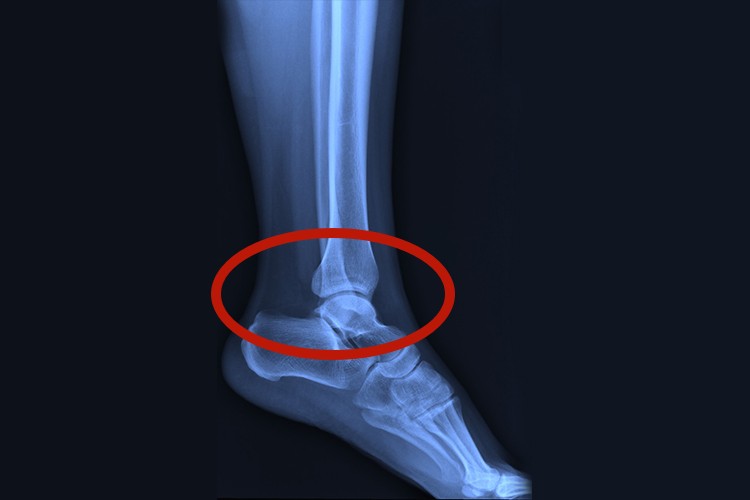

足踝是踝关节部位,位于小腿和足之间,由胫腓骨下端的关节面和距骨滑车构成。

足踝是指踝关节,位于小腿和足之间,俗称脚腕,由胫腓骨下端的关节面和距骨滑车构成。关节囊内侧有1条韧带,外侧有3条韧带,加固关节,共同组成关节窝,使足踝能够灵活转动。

踝关节囊前后壁薄而松弛,内外有4条韧带和软组织,可使足尖向上或向下运动,或是绕矢状轴做轻微的收、展运动。但关节外侧韧带较为薄弱,常因猛力使足内翻过度而损伤,造成韧带拉伤,或因关节松动,稳定性较差而导致踝关节扭伤。